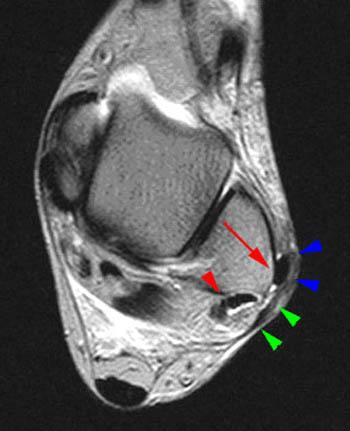

The peroneal tendon originates in the lateral compartment of the leg and travels around the lateral malleolus posteriorly and inferiorly 2 ( . One peroneal tendon attaches to the outer part of the midfoot, while the other runs under the foot and attaches near the inside of the arch. The peroneal tendons complex includes the peroneus brevis muscle and tendon (pb), peroneus longus muscle and tendon (pl), the common synovial . The "fleck sign" is an indication for peroneal tendon subluxation. Muscle activation in people with chronic ankle instability. The peroneal tendons are located in the foot, attaching muscle to bone. The peroneal tendons are positioned posterolaterally and function as evertors and plantar flexors as well as dynamic stabilizers of the foot and ankle. The peroneus longus and brevis muscles lie within the lateral.

One peroneal tendon attaches to the outer part of the midfoot, while the other runs under the foot and attaches near the inside of the arch. Peroneal Tendon Dislocation And Superior Peroneal Retinaculum Injury Radsource

Peroneal Tendon Dislocation And Superior Peroneal Retinaculum Injury Radsource from radsource.us